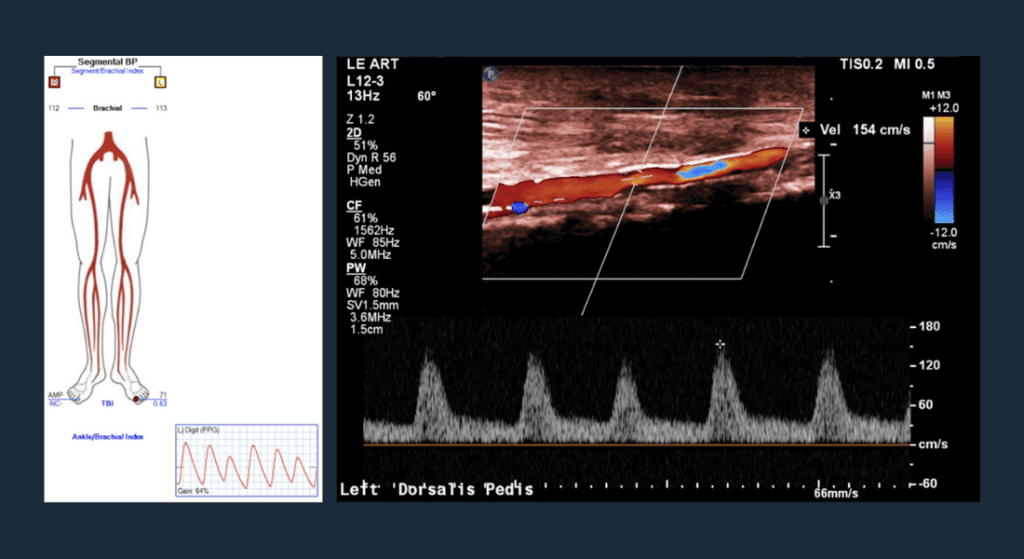

Post-op Vascular Lab Testing

Great toe pressure restored to 71mmhg; widely patent dorsal pedal vessel.